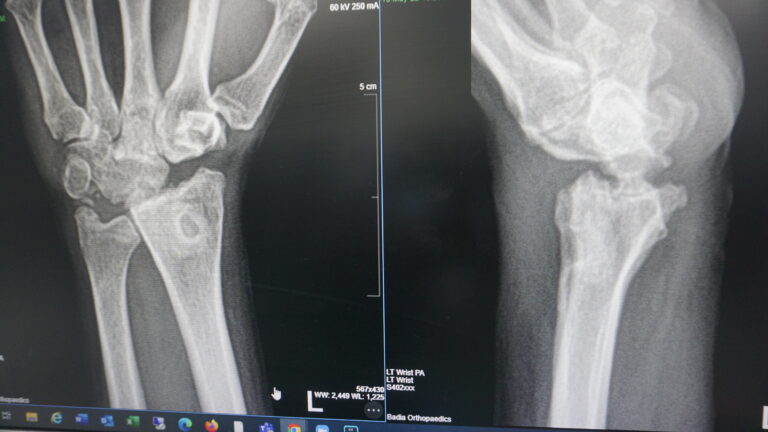

- post-traumatic arthritis: Individuals who have experienced traumatic injuries to the wrist, such as fractures that involve the joint surface, may develop post-traumatic arthritis over time. This condition can lead to pain and loss of joint function, making wrist replacement a potential solution.